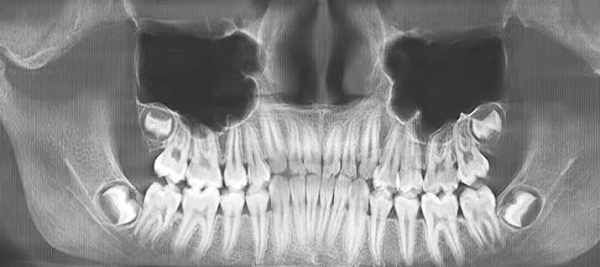

Специалист рассказал о стадиях формирования 8-х зубов, которые всегда следует учитывать при принятии решения об их удалении (см. рис. 1.): А — зачаток зуба, кальцификации нет, В — начальная кальцификация бугров, С — кальцификация бугров, D — начало кальцификации коронки, Е — полная кальцификация коронки, F — начало формирования корней, G — полное формирование корней, H — закрытие верхушечных отверстий корней.

Рисунок 1. Стадии формирования 8-х зубов по данным ортопантомографии.